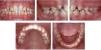

Intraoral analysis. Microdontic lateral incisors, a 0.5mm deviation to the left of the lower dental midline in relation to the upper dental midline, molar and canine class I, mild lower crowding and arch form were observed (Figure 2).